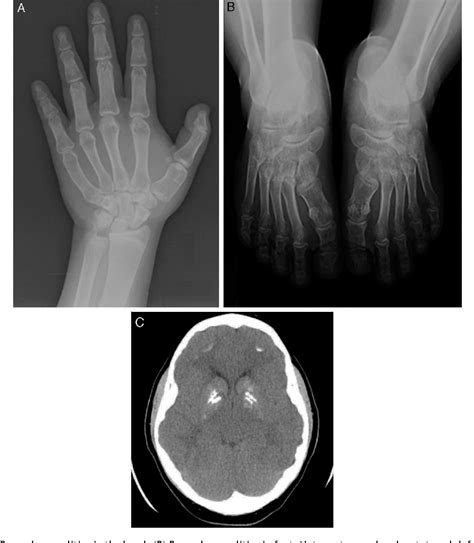

• Brachydactyly: Shortening of the bones in the hands and feet, particularly the fourth and fifth metacarpals and metatarsals.

• Subcutaneous Ossifications: These are small, hard lumps of bone that form under the skin, often in the hands, feet, and other areas.

Diagnostic Methods

Diagnosing AHO involves a combination of clinical evaluation, genetic testing, and laboratory tests. The diagnostic process typically includes:

• Clinical Evaluation: A thorough physical examination to assess the characteristic features of AHO, such as short stature, obesity, and brachydactyly.

• Genetic Testing: Molecular genetic testing to identify mutations in the GNAS gene. This can confirm the diagnosis and differentiate between PHP1a and PPHP.

• Laboratory Tests: Blood tests to measure levels of calcium, phosphorus, and parathyroid hormone. Individuals with PHP1a may have low calcium levels and high phosphorus levels.